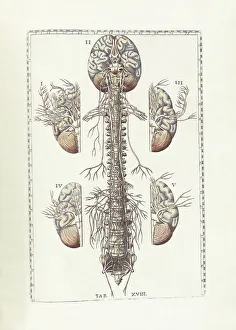

The central nervous system, the intricate network that governs our every thought and movement, is a marvel of complexity. From the delicate cerebellum tissue to the detailed light micrograph capturing its essence, we are reminded of its importance in maintaining balance and coordination. Anatomy comes alive as we explore the human brain from an inferior view. The intricacy of brain fibers is revealed through DTI MRI scans like C017/7099 and C017/7035, showcasing their vital role in transmitting information throughout this extraordinary organ. Artistic renderings bring us closer to understanding the medulla oblongata's significance within the brain. Its portrayal in various artworks allows us to appreciate how it controls essential functions such as breathing and heart rate. As we delve deeper into studying the central nervous system, models of the human brain provide invaluable insights into its structure and organization. Lateral views reveal countless regions responsible for cognition, emotion regulation, sensory perception, and motor control. Microscope slides offer glimpses into nerve cells' intricate architecture—a testament to their ability to transmit electrical signals at lightning speed. Meanwhile, glial stem cell cultures captured under a light microscope remind us of their crucial role in supporting neuronal function. Finally, artistic representations unveil the limbic system's enigmatic nature—an interconnected web responsible for emotions and memory formation. These captivating artworks allow us to visualize this complex network within our brains. Exploring these hints provides a glimpse into the awe-inspiring world of our central nervous system—the very foundation upon which our thoughts, actions, memories reside—reminding us just how remarkable our brains truly are.